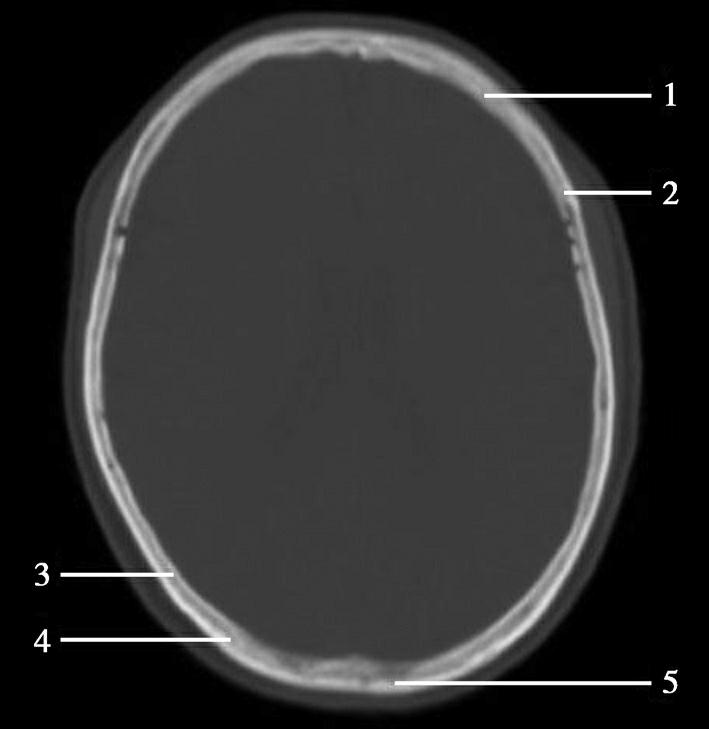

图1-2-2 颅底层面(骨窗)

A.横断面;B.横断面标注

1.鼻骨;2.筛窦纸板;3.颧骨眶突;4.翼腭窝;5.蝶骨大翼;6.卵圆孔;7.破裂孔;8.颞骨颧突;9.棘孔;10.斜坡;11.颞骨岩部;12.乳突;13.颈静脉孔;14.枕乳突缝;15.枕骨;16.枕内隆凸

层面前部呈开口向前的“V”字形,正中为鼻中隔,向两侧依次为筛窦和眼眶,眼眶内前部为眼球,后部为眶脂体。翼腭窝位于眼眶后部,窝内含有脂肪并有上颌神经通过。层面中部为蝶骨体,蝶骨体中部可见含气蝶窦,蝶窦后方为枕骨基底部,两者呈前后关系,其上面构成斜坡。蝶窦两侧为蝶骨大翼,其后外侧缘处由前向后可见卵圆孔和棘孔,分别有下颌神经和脑膜中动脉通过。斜坡外侧、岩骨尖前方为破裂孔。蝶骨大翼与眶外侧壁的颧骨借颧弓相连,颧弓和蝶骨大翼之间有咬肌及颞肌。层面中部外侧为外耳道。颞骨岩部呈“八”字形,相互之间借破裂孔软骨、蝶岩软骨结合和岩枕软骨结合连接。岩部后外侧的乳突部内可见乳突小房,乳突部与枕骨相接。岩骨后部可见颈静脉孔,内有颈内静脉、舌咽神经、迷走神经和副神经通过。层面后部为颅后窝,其内可见延髓,延髓前方为延髓前池,内有椎动脉,后外侧为小脑半球下部,后方为第四脑室、小脑扁桃体及小脑蚓部。

破裂孔、卵圆孔、棘孔及斜坡等均为重要的解剖结构,临床常见疾病如鼻咽癌常侵犯上述结构(图1-2-3)。颈静脉孔区较常见的肿瘤为颈静脉球瘤,常伴有颈静脉孔及其邻近骨质的破坏(图1-2-4)。